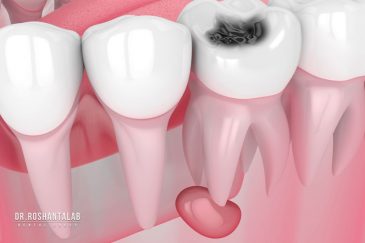

از عصب کشی و درمان ریشه دندان گرفته تا جراحی لثه و کشیدن دندان، تمامی مراحل توسط متخصص ترمیم دندان مدیریت میشود. ارائه باکیفیتترین خدمات ترمیم دندان برای سلامتی شماست.کاشت ایمپلنت فوری دندان